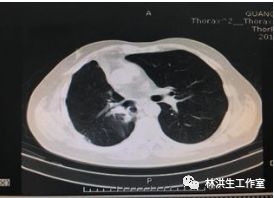

【诊断】右肺腺癌术后,左肺门及纵膈淋巴结转移,多程化疗后 Ⅲ期

【现病史】患者2011年8月诊断右肺上叶中低分化腺癌Ⅲ期,行右肺上叶切除术后行5周期GP方案辅助化疗,后定期复查胸部CT,病情稳定。2015年1月22日胸部CT提示:右肺下叶近肺门可见形态不规则肿物影,大小约3*3.5cm,纵膈及左肺门可见多发淋巴结影,考虑进展,予中西医结合治疗至今,病灶控制稳定,体力状况PS 100分。